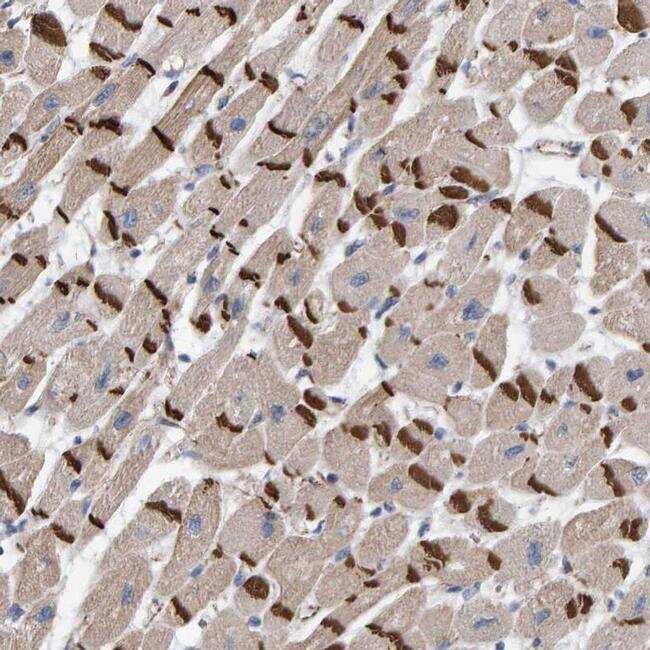

Supportive validation

- Submitted by

- Invitrogen Antibodies (provider)

- Main image

- Experimental details

- Immunohistochemical analysis of KRBA2 in human heart muscle using KRBA2 Polyclonal Antibody (Product # PA5-54619) shows strong positivity in the intercalated discs.